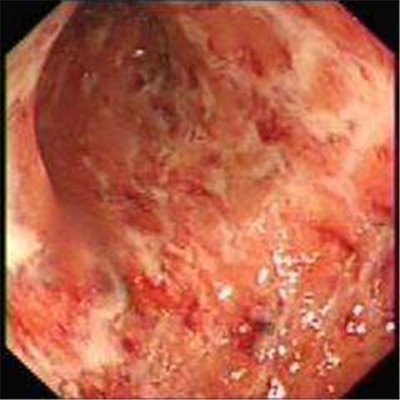

結(jié)腸炎腸鏡下的表現(xiàn):

4. 結(jié)腸鏡檢查:發(fā)現(xiàn)病變部位彌漫性充血、水腫、糜爛、潰瘍,脆性增加,表面常附有膿性分泌物及血液,多發(fā)性假息肉及腸腔狹窄、橋形黏膜,結(jié)腸袋變淺或消失。